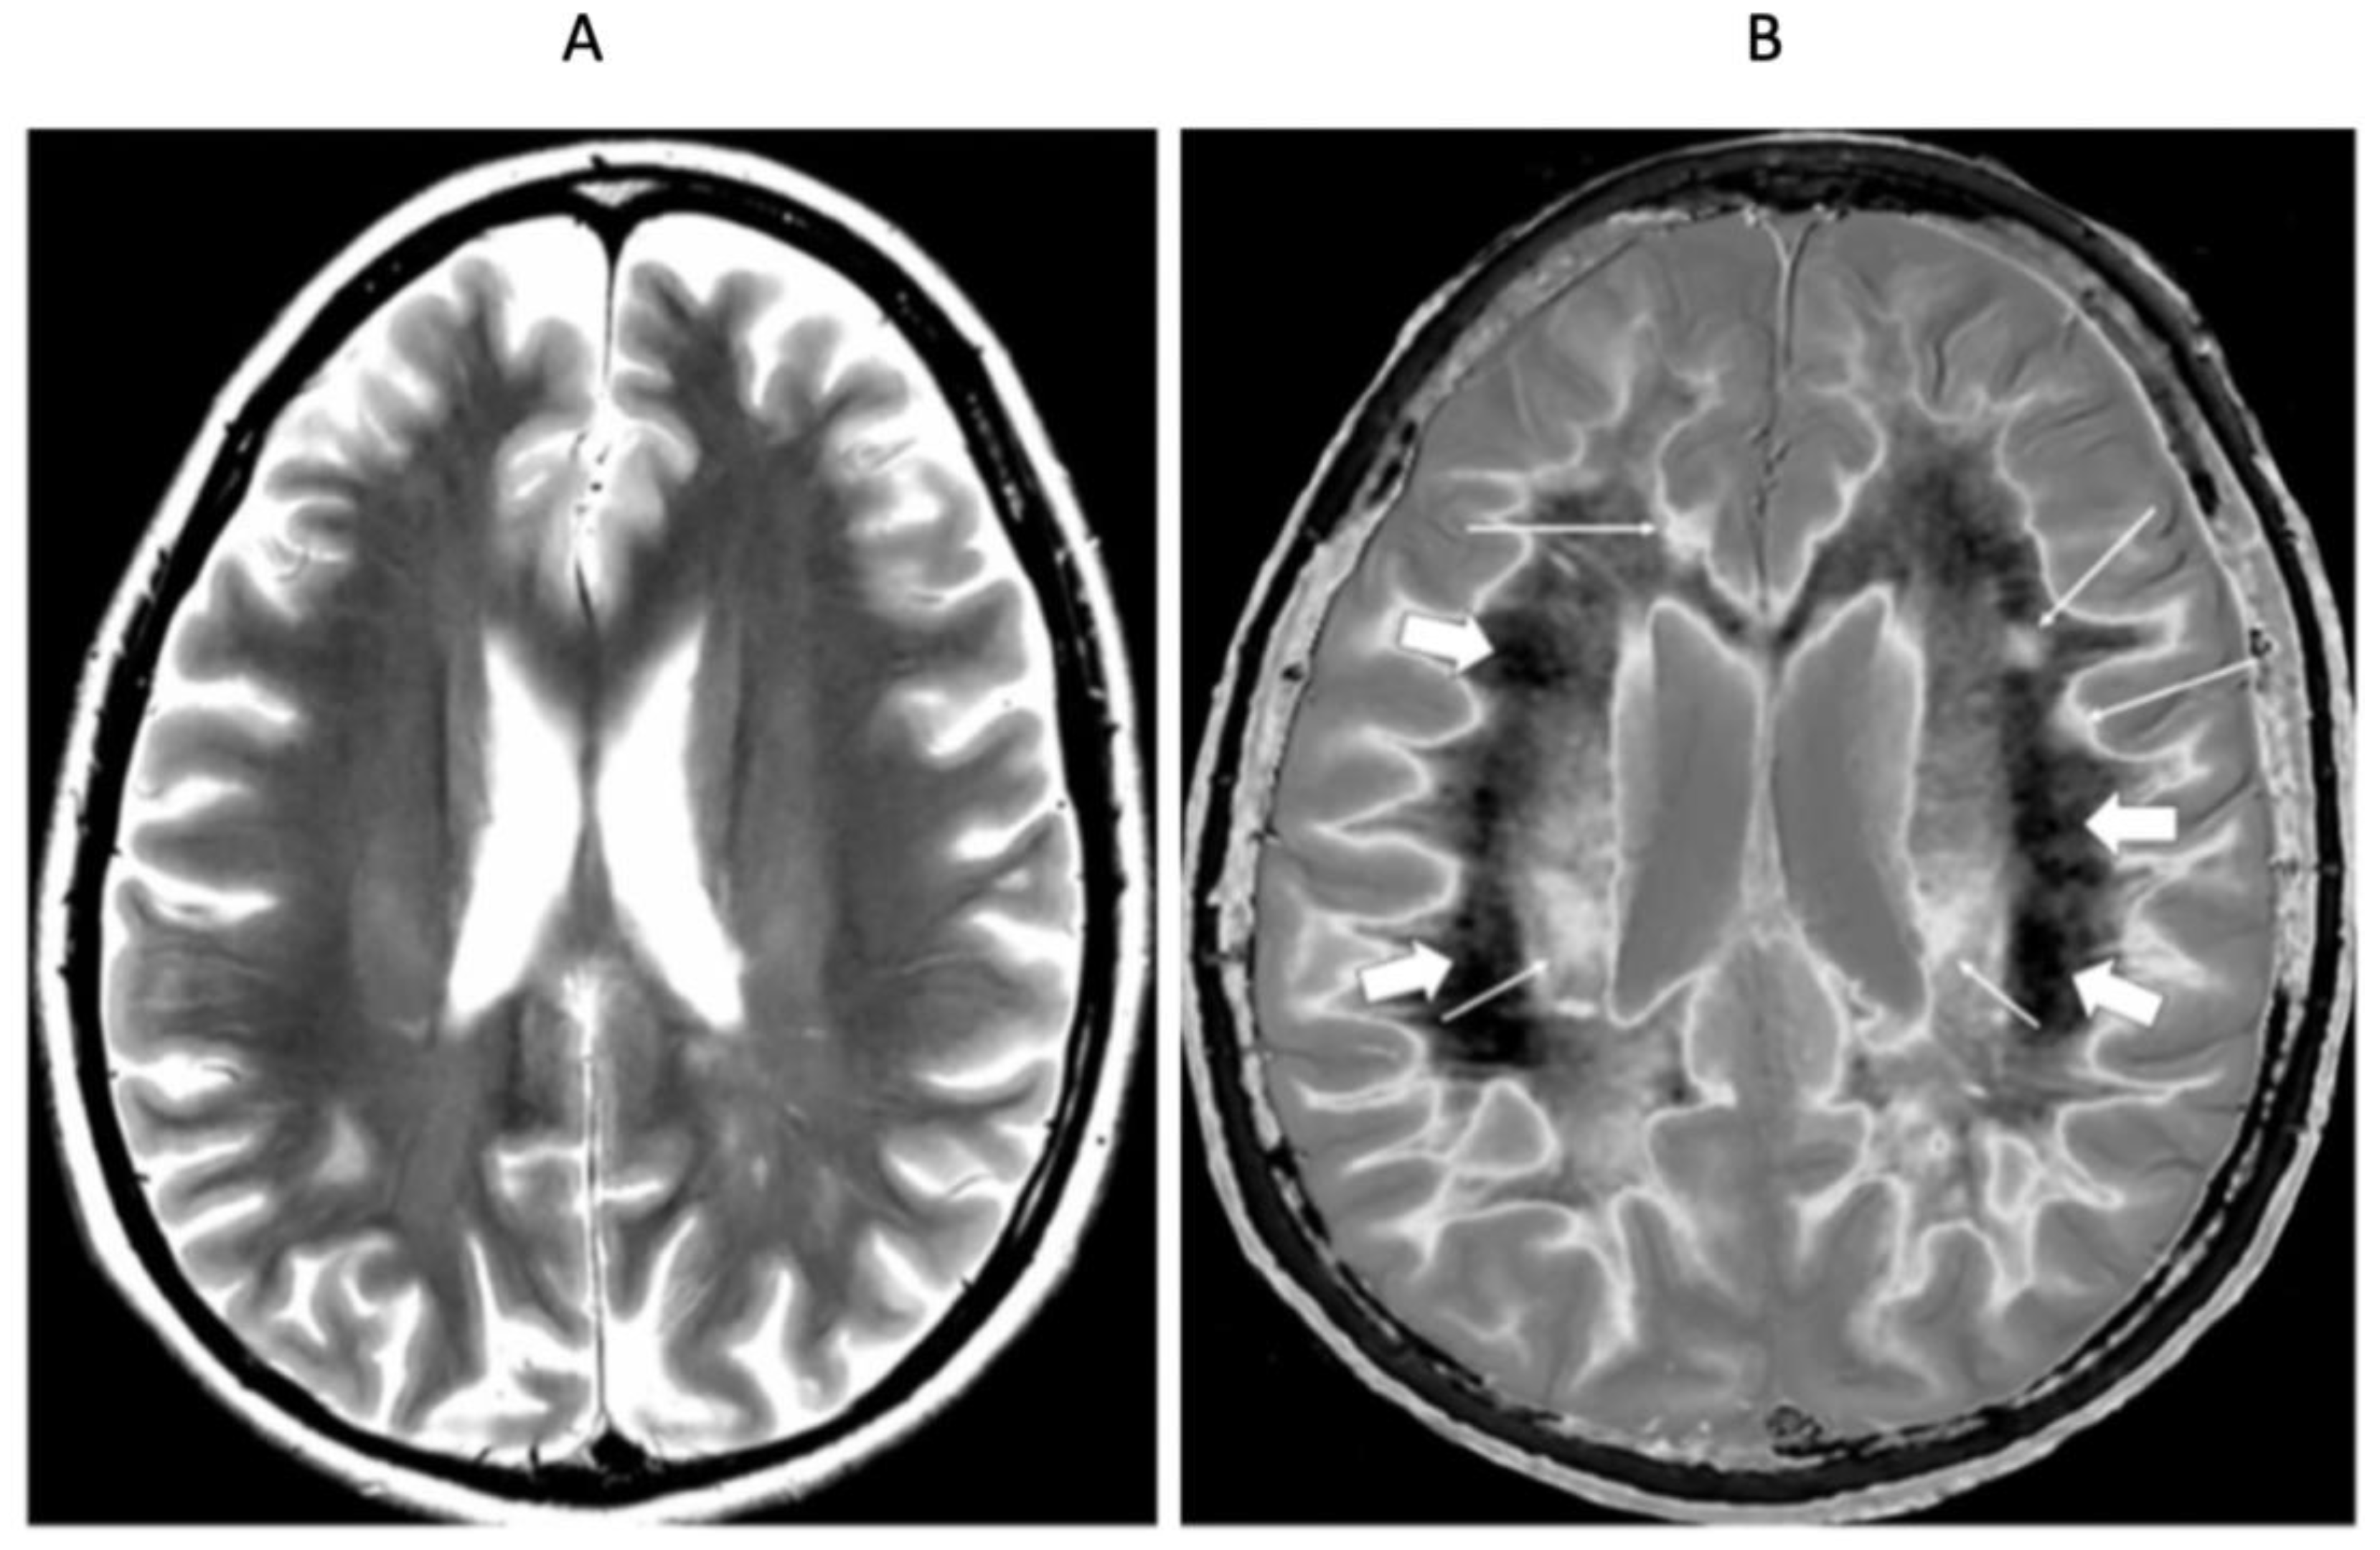

Figure 6 shows mid-ventricular images of a 41-year-old female patient with MS in remission. No abnormality is seen on the T2-wSE image (Figure 6A). On the narrow mD dSIR image (Figure 6B), normal peripheral white matter is dark and has a low signal (thick arrows). The more central superior longitudinal fasciculi show a higher signal with a gradient of signal decreasing from posterior to anterior. Within them are the corticospinal tracts (short thin arrows). Three focal lesions are seen in the peripheral white matter and at the leucocortical junctions (long thin arrows).

Figure 6.

Forty-one-year-old female with MS in remission. Comparison of 2D T2-wSE (A) and narrow mD dSIR (B) images. No abnormality is seen on the T2-wSE image, but three focal lesions are seen on the dSIR image (long thin arrows). The corticospinal tracts are also seen (short thin arrows). The normal superior longitudinal fasciculi are of intermediate (posterior) to low (anterior) signal in (B). More peripheral white matter is normal and has a low signal in (B) (thick arrows). A high signal boundary is seen between white matter and cortical grey matter as well as between white matter and CSF around the lateral ventricles in (B).

At a supraventricular level in the same patient (Figure 7), the T2-wSE image is again normal (Figure 7A). The corresponding narrow mD dSIR image shows only a small region of low signal normal white matter (dark arrow). The corticospinal tracts are seen (short thin white arrows), as well as a lesion (long thin white arrow). There are widespread asymmetric and patchy abnormalities in the white matter.

Figure 7.

Forty-one-year-old female patient with MS in remission (as for Figure 6). Two-dimensional T2-wSE (A) and narrow mD dSIR (B) images at the same level. No abnormality is seen in (A). A focal lesion is seen in (B) (long thin white arrow) and the corticospinal tracts show a high signal (short thin white arrows). In addition, there is widespread, patchy increased signal in white matter (short thick white arrows) with only a small region showing a normal or near normal low signal (long black arrow). High contrast and high spatial resolution contrast are seen at the boundaries between normal white matter and normal gray matter in (B). These features are less obvious in areas where the white matter shows abnormal high signal.